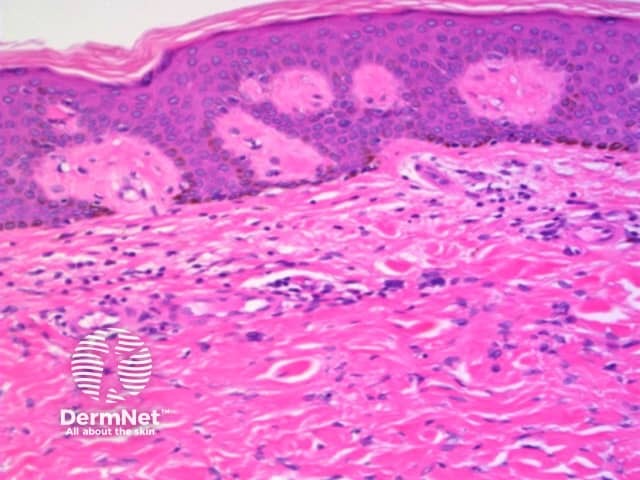

The histological features of melanocytic naevi are:

Compound naevus